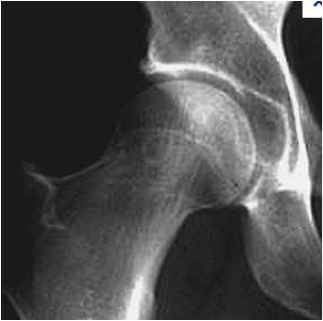

Radiographie d'une hanche normale

Hanche normale